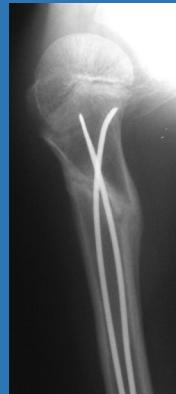

| K-wire (Kirschner Wire) | Indications: Pediatric fractures, small bone fractures in adults. Advantages: Easy to apply/remove. Disadvantages: Not stable alone, risk of infection. | , , , , , ![]() |

| Inter-locking Nail | Indications: Fractures of long bones. Advantages: Minimally invasive, preserves fracture hematoma, allows early weight-bearing on lower limb. | , , , ![]() |